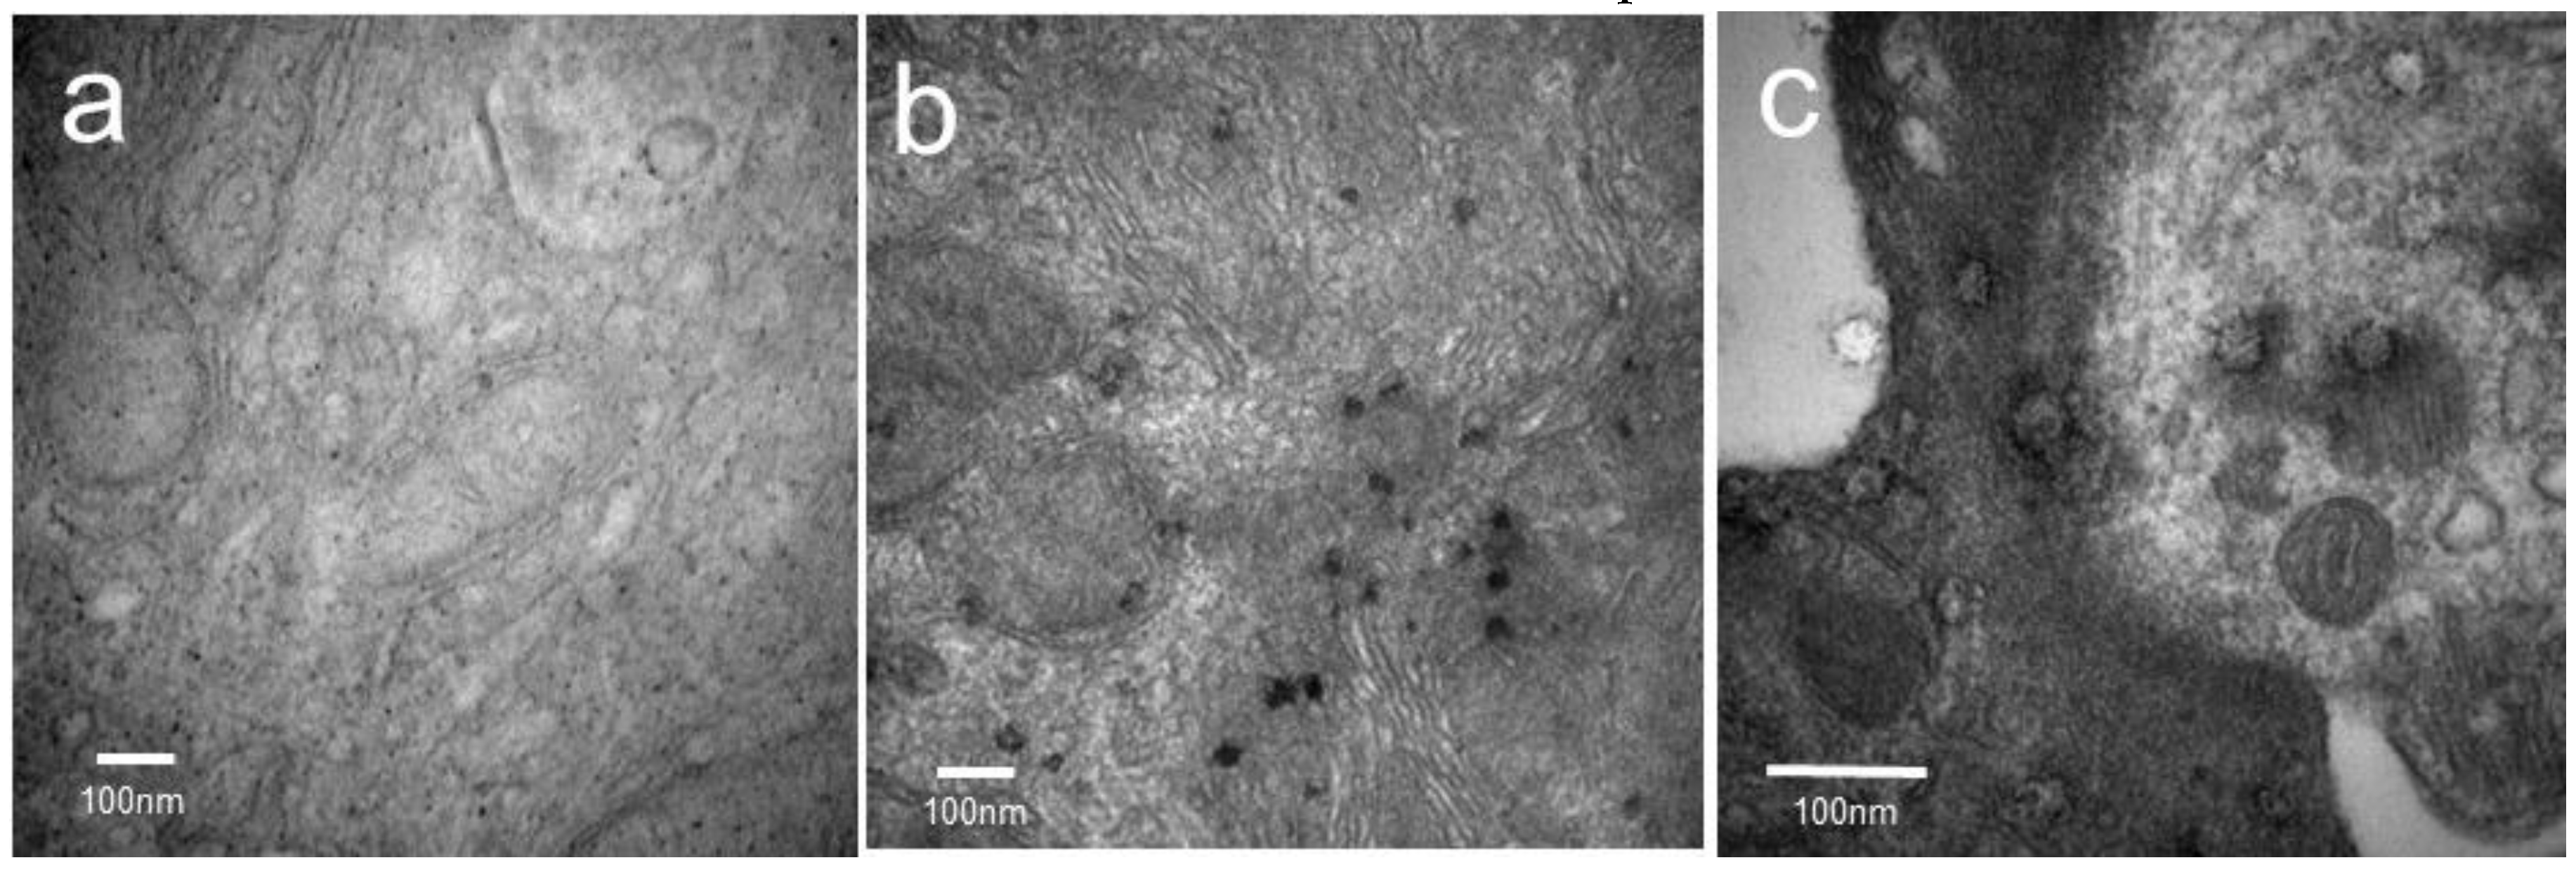

The ability of iron oxide-modified NE to be visualized after nasal administration was also tested. In these experiments 10 µL (5 µL/nare) of iron oxide-modified NE was administered slowly to the nares, with control mice receiving NE alone. Four hours after administration, TEM studies were done. A signal was detected in the septum of mice administrated with iron oxide-modified NE as darker shadows in TEM imaging (Figure 5b). However, the iron signal could not be observed in the septum of mice treated with NE alone (Figure 5a). At higher resolutions, multiple larger aggregates of iron oxide cores in the mouse septum were recorded (Figure 5c). These findings demonstrate that iron oxide-modified NE is detectable in the mouse nasal septum at least 4 h after administration, and that iron oxide can be used to track NE at least as far as the nasal septum.

Figure 5. Nasal epithelia structure following the administration of NE and iron oxide-modified NE by TEM. (a) Nasal septa from mice treated with NE alone; (b) nasal septa from mice treated with iron oxide modified NE; (c) nasal septa from mice treated with iron oxide modified NE at the higher resolution.